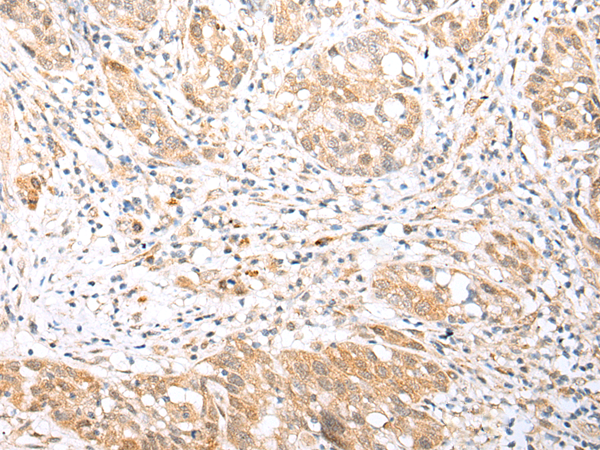

The image is immunohistochemistry of paraffin-embedded Human ovarian cancer tissue using P05670(BCL2L11 Antibody) at dilution 1/30. (Original magnification: ×200) |

The image is immunohistochemistry of paraffin-embedded Human gastric cancer tissue using P05670(BCL2L11 Antibody) at dilution 1/30. (Original magnification: ×200) |